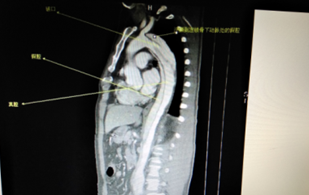

术前CT检查(显示为主动脉夹层)

“治疗方式的选择主要根据主动脉夹层的类型而定。”魏宇进一步说到。就目前的治疗现状而言,对于Stanford B型主动脉夹层,以微创腔内治疗为主。传统的主动脉夹层微创腔内修复术在技术上要求主动脉上至少有1.5cm的锚定区,以防止近端封堵不完全,出现内漏。但是,随着腔内修复器材的改进和腔内修复技术的进步,这一指征已扩大,可以通过杂交手术或各种腔内修复巧术(烟囱、开窗、模块分支支架)来治疗主裂口距左锁骨下动脉开口1.5cm以内的Stanford B型主动脉夹层。腔内治疗术后需要更严密的随诊,定期进行CT检查,避免内瘘等并发症的发生。另外,对于有着明确腔内治疗适应症的患者,或对于全身状态不佳,难以耐受外科手术的患者,腔内治疗无疑是一个很好的选择。